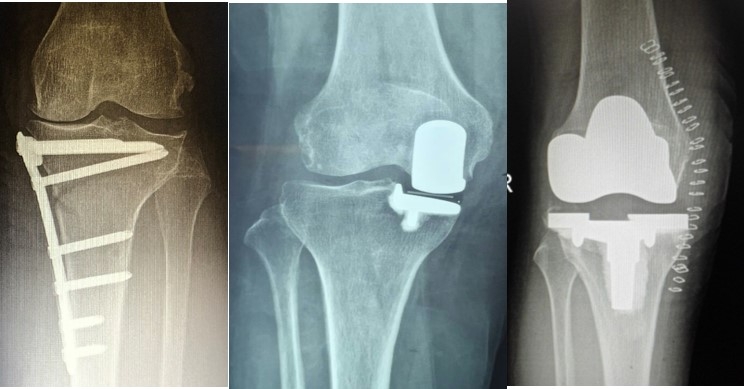

病例3:男,70岁,主诉右膝关节疼痛1年余。查体右膝无肿胀畸形,膝活动度0-120°,内侧间隙压痛。

已经累及44%的股骨内侧髁病变,半月板轻度突出,内侧后角水平撕裂

MRI上深度>20mm

治疗选择保守还是手术?

保守治疗4个月后复查

保守治疗后效果欠佳,坏死范围扩大、塌陷

翻修手术选择截骨矫形还是单髁置换?

最终选择截骨矫形

术后1年1个月

术后2年1个月拆钉

内侧半月板突出未见明显进展